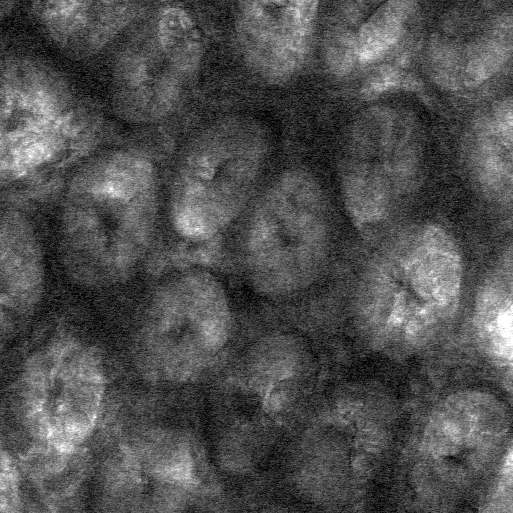

Performing their experiments in mice, the team tested the effects of polymers, which include dietary fiber as well as therapeutics such as medicines for constipation. The researchers fed some mice a diet rich in polymers and others (the controls) a polymer-free diet. Using a technique called confocal reflectance microscopy they measured the thickness of the gut gel and the degree to which the gel was compressed as a result of the consumed polymers. Mice given a high-polymer diet, they found, had a more compressed gel layer.

"The gel is like a sponge with holes that let material through," says the paper's lead author, Sujit Datta, a postdoctoral scholar in the laboratory of Rustem Ismagilov, Ethel Wilson Bowles and Robert Bowles Professor of Chemistry and Chemical Engineering. "We are seeing that polymers, including dietary fiber, can compress the gel, potentially making the holes smaller, and we think that this might offer protective benefits," Datta adds.

In addition, the researchers applied different kinds of polymers—including dietary fibers like pectin, found in apples—directly to the gel lining to test its response. All of the polymers tested compressed the gel layer.

The researchers also found that dietary fiber and gut bacteria—which are part of a community of microorganisms collectively known as gut microbiota—can work together to influence how the gut gel changes shape. They performed the same polymer/fiber experiments in germ-free mice, which are mice carefully raised to not have any bacteria in their gut. The results showed that the polymers compressed the gut gels of these germ-free mice to a greater degree. This implies that species of bacteria in our gut that are known to break down polymers can weaken the compressing effect.